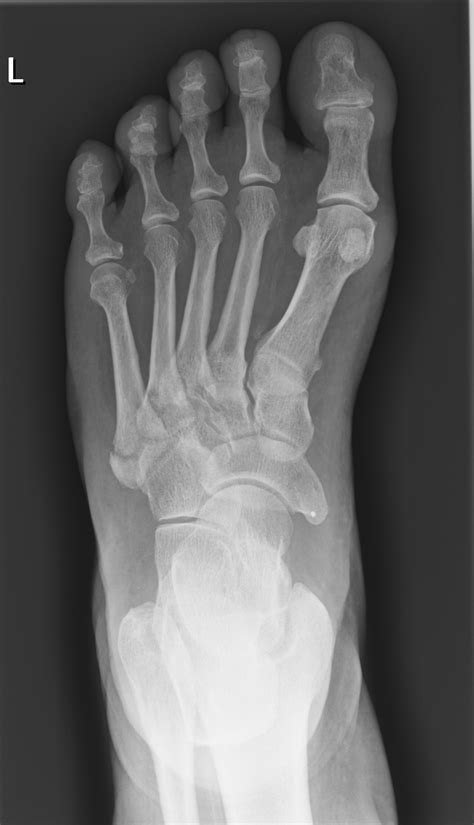

Diagnosing a 5th Metatarsal Base Fracture

Diagnosing a 5th metatarsal base fracture typically involves a combination of physical examination and imaging tests. The diagnostic process may include:

• Physical Examination: A healthcare provider will assess the foot for swelling, tenderness, and range of motion.

• X-Rays: Imaging tests to visualize the bone and identify any fractures.

• CT Scans or MRIs: In some cases, more detailed imaging may be required to assess the extent of the injury.